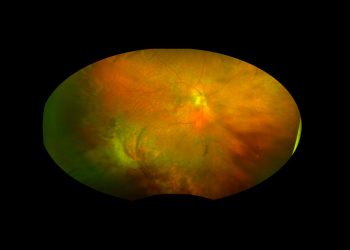

Regresión espontánea de una masa subretiniana periférica: a propósito de un caso de PEHCR

Autores: Ingrid Pita-Ortiz, MD1, Octavio Turcio-Aceves MD1, Mauricio Bayram-Suverza, MD1. Departamento de Retina y Vítreo, Fundación ...